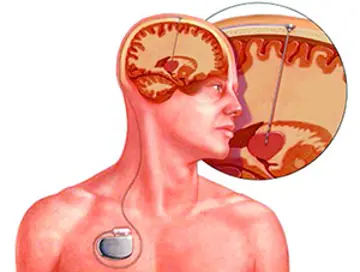

مغز و اعصاب - صفحه 15